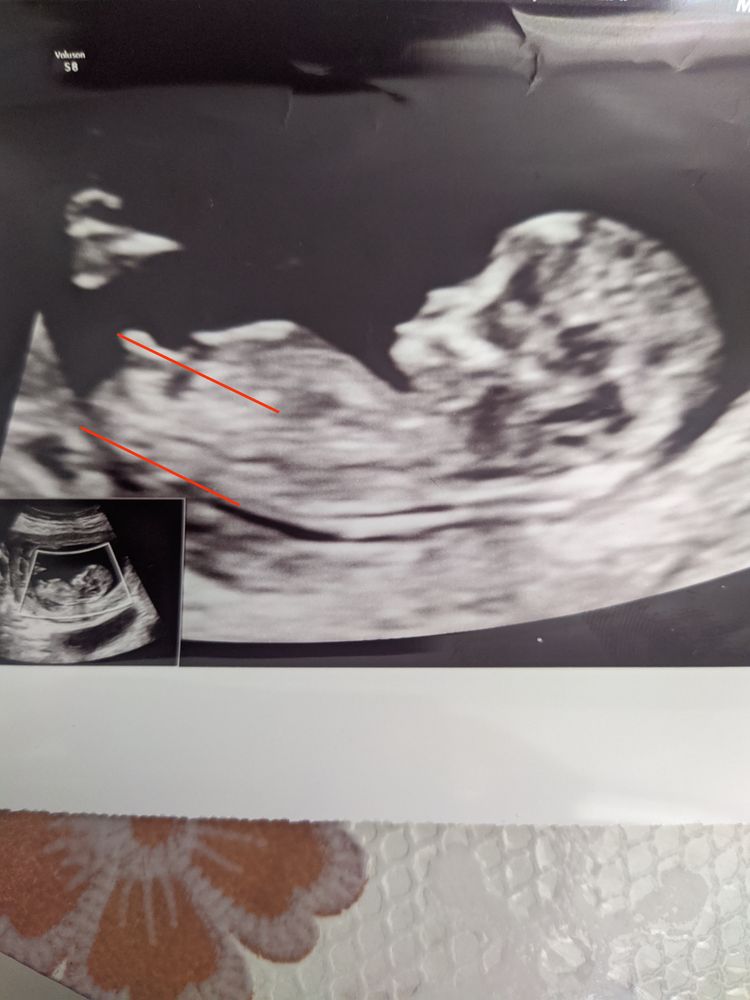

Помогите определить пол ребенка

А я думаю, что девочка. Моя на УЗИ имела очень похожий вид полового бугорка

Видела такую же почти фотку с линиями там была девочка

Мальчик🙂, пипетка совсем на клитор не похожа....

У меня на первом скрининге прям один в один такой же бугорок под таким же углом. УЗИстка сказала, что хоть и угол «девочкин» размер имеет большее значение, а размерчик бугорка больше мальчиковый)) жду вот тоже следующего УЗИ через пару недель уже окончательно увидеть кто там

У меня такое фото мальчика)